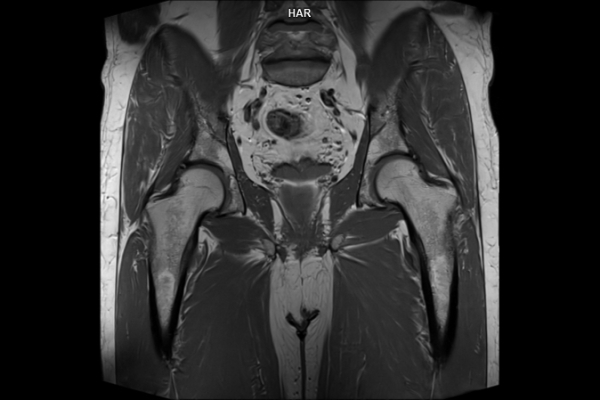

Detailbild MRT

• Bildgebende Endometriose-Abklärung

Wir bieten ein breites Spektrum an Untersuchungen an, von Standarduntersuchungen der Gelenke, Organe oder großflächigen Körperregionen bis zu Spezialuntersuchungen zum Beispiel des Herzen oder der Gefäße. Zusätzlich werden Angiographien (Darstellung von Blutgefäßen), Endometriose-Abklärungen und Mamma-Untersuchungen durchgeführt. Genauere Details können Sie der MRT/CT-Übersicht und der Preisliste entnehmen, oder Sie wenden sich direkt an unser Team, das Sie gerne zur passenden Untersuchung berät.

Die MRT (Magnetresonanztomographie) arbeitet mit Magnetfeldern und Radiowellen und eignet sich besonders für Untersuchungen der Weichteile wie Gehirn, Muskeln oder Gelenke. Die CT (Computertomographie) nutzt Röntgenstrahlen und liefert schnelle, hochauflösende Bilder, insbesondere für Knochen, Lunge oder innere Organe. Die Wahl der jeweiligen Untersuchung richtet sich an das individuelle Krankheitsbild und wird bei der Überweisung festgelegt.